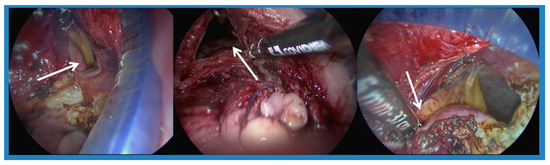

Novel Application of the Lagis LapBase Cap in Transvaginal NOTES Hysterectomy: Surgical Outcomes and Cost-Effectiveness in 107 Cases

Objectives: Transvaginal Natural Orifice Transluminal Endoscopic Surgery (vNOTES) offers significant benefits in hysterectomy, including reduced postoperative pain, minimal scarring, and faster recovery. However, the cost and accessibility of surgical ports can be limiting factors. This study aimed to evaluate the feasibility, outcomes, and [...] Read more.

Objectives: Transvaginal Natural Orifice Transluminal Endoscopic Surgery (vNOTES) offers significant benefits in hysterectomy, including reduced postoperative pain, minimal scarring, and faster recovery. However, the cost and accessibility of surgical ports can be limiting factors. This study aimed to evaluate the feasibility, outcomes, and cost-effectiveness of using the Lagis LapBase Cap as an alternative port system in 107 vNOTES hysterectomy cases at a single institution. Methods: A retrospective analysis was conducted on 107 patients who underwent vNOTES hysterectomy between January 2017 and April 2022. Patients with benign gynecologic conditions and no suspected malignancy or deep infiltrating endometriosis were included. The Lagis LapBase Cap was used for access via an Alexis wound retractor. Surgical parameters—including operation time, estimated blood loss, and length of hospital stay—were analyzed by uterine weight, BMI, and obstetric history. Results: Of the 107 cases, 104 were completed using vNOTES, with only 3 conversions to laparoscopy. The average operation time was 88 min, and the mean estimated blood loss was higher in patients with larger uteri or BMI ≥ 24. Nulliparous women and those with a history of multiple cesarean sections also had longer operation times. There were no major complications, and most patients were discharged within three days postoperatively. Conclusions: The Lagis LapBase Cap is a practical and cost-efficient tool for vNOTES hysterectomy. It provides reliable sealing and instrument access, while maintaining favorable surgical outcomes. Patient selection based on uterine size, BMI, and delivery history may help optimize procedural efficiency. Full article